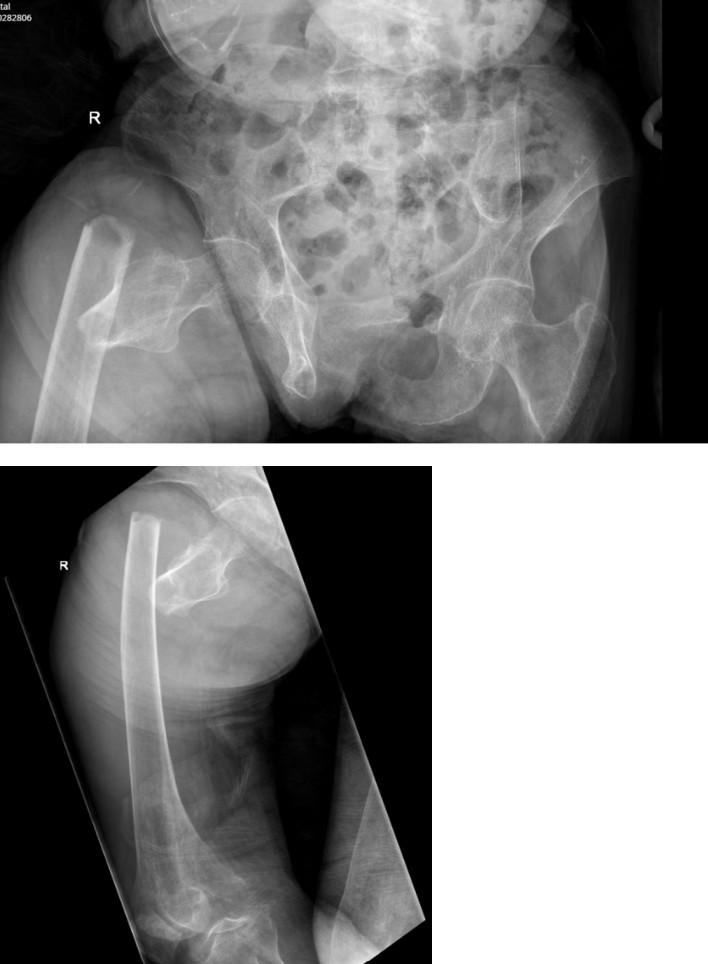

Elder abuse

An 83-year-old female, from a non-English speaking background, is brought in with increasing right thigh pain and swelling after falling …

Elder abuse assessment

An 83-year-old man is brought in from home following a fall three days prior. He lives with his son who …